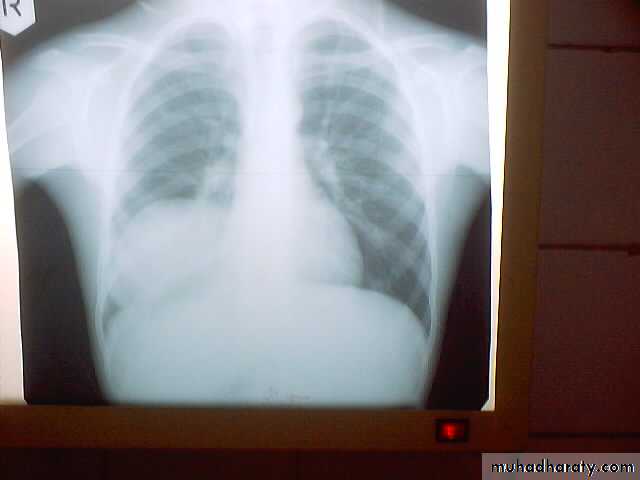

• Pulmonary Echinococcosis (Hydatid Cyst)

• Hydatid disease of the lung is caused by the small tape worm (Taenia Echinococcus ) or (Echinococcus Granulosis) .Hydatid cyst means cyst full of water .It has a life cycle between dogs & sheep .Parasites in the elementary tract of the dog shed ova that excreted in the dog faeces , contaminated the food of the sheep in which hydatid cyst will develops in the viscera . Including the lung .Infected sheep when slaughtered and its entrails are eaten by dogs , the life cycle is completed .When a human being hands or food become contaminated with canine fecal material containing ova which will be ingested .The parasitic larva burrow through the gastric mucosa and are carried to the liver in the portal venous circulation where most of them filtered out to form hydatid cyst of the liver , some escape the liver & lodge in the lung to form one or more hydatid cyst which grows slowly or rapidly over years .

• The cyst consists of a germinal layer & cyst fluid containing broad capsule & scoleses . A cellular white hyaline layers are laid down outside the cyst so that the cyst is enclosed by a laminated cyst membrane .As the cyst enlarged , it usually reaches the pleural surface . Compression of the lung tissues produces a thin fibrous layer of atelectatic lung tissue around the cyst (capsule , pericyst or adventia)

• A-Asymptomatic• Any smooth homogenous opacity of uniform density with clear cut border and little or no reaction around it on a chest X-Ray is a hydatid cyst unless proved the other wise .

• Radiological Findings

• 1-Smooth homogenous opacity (Intact H.C).• 2-Partial rupture (per vesicular pneumocyst).

• 3-Complete rupture (Water –lilly sign) .

• 4-Formation of lung abscess(Air –fluid level) .

• 5-Completely coughed out cyst(empty cavity )

• 6-Rupture into the pleura (hydropneumothorax)